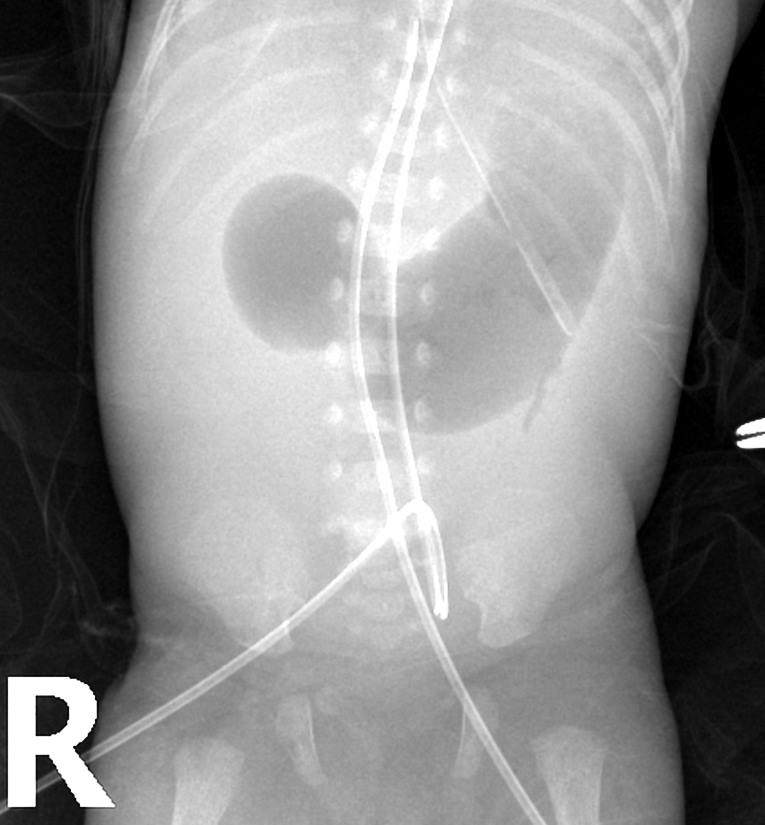

P DBL BUBBLE